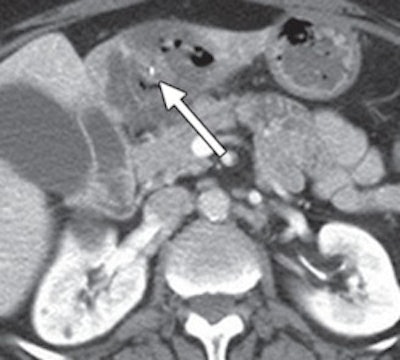

The remaining three patients presented with abdominal pain and underwent CT scans. In two patients, the wire perforated the small intestine. The metal piece perforated through the stomach and into the liver of the third patient and was surrounded by a large hepatic abscess. Laparoscopy was performed on the basis of the CT and clinical findings, and the bristle was removed through surgery.

Grant said that CT is the hospital's "first-line imaging modality" in the ER for abdominal pain. Patients in whom the metal bristles were found in the abdomen were all diagnosed on CT.

"One critical element that helped us a great deal is that we no longer give oral contrast to patients in the ER who are undergoing CT," Grant added. "Oral contrast is bright and the bristles are bright. The oral contrast theoretically could mask or obscure one of the bristles in the abdomen. So I think it is helpful that we stopped giving oral contrast a few years ago."